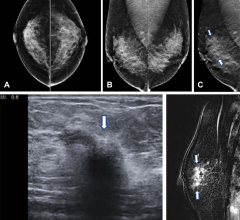

March 15, 2023 — In a study of over a million women, digital breast tomosynthesis (DBT) showed improved breast cancer ...